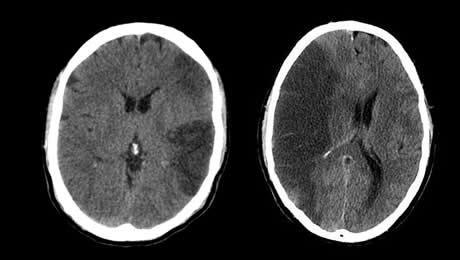

- Le score de Glasgow est un outil d’évaluation initial utile comme facteur prédictif de l’évolution à moyen terme de la vigilance, essentiellement en cas d’hémorragie cérébrale ou d’Infarctus Cérébral sévère.